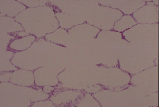

呼吸器12. ヒトの肺の表層部 |